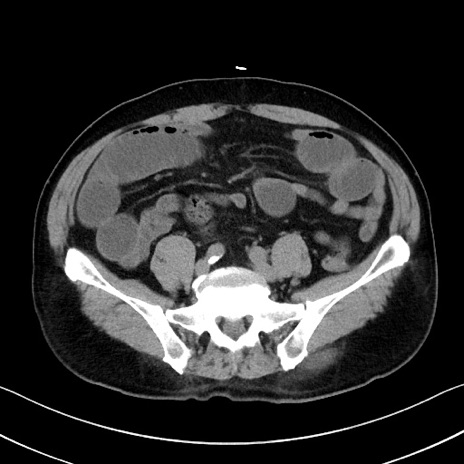

症例35(横断像)

【症例】70歳代 男性

【主訴】腹部膨満、嘔吐

【現病歴】昨日より腹部膨満感出現。本日増悪し、仙痛出現。嘔吐あり、受診。

【既往歴】糖尿病、胆摘後

【身体所見】BP 149/80mmHg、HR 74/min、BT 35.9℃、腹部:膨満、軟、圧痛なし。腸雑音減弱あり。上腹部正中切開瘢痕あり。

【データ】WBC 13500、CRP 1.72